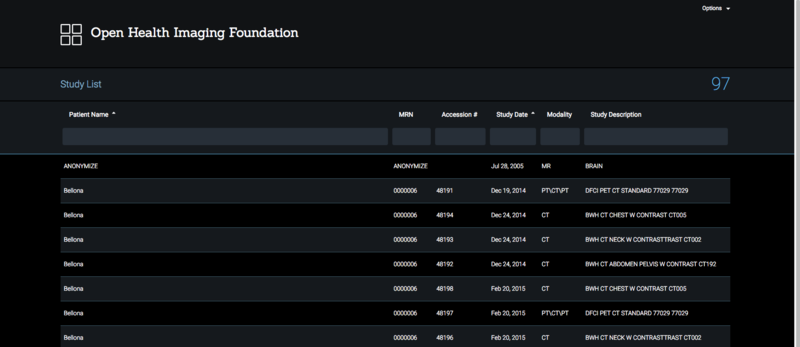

Project Week 25/DICOM Segmentation Support for Cornerstone and OHIF Viewer

Home < Project Week 25 < DICOM Segmentation Support for Cornerstone and OHIF Viewer

Illustrations